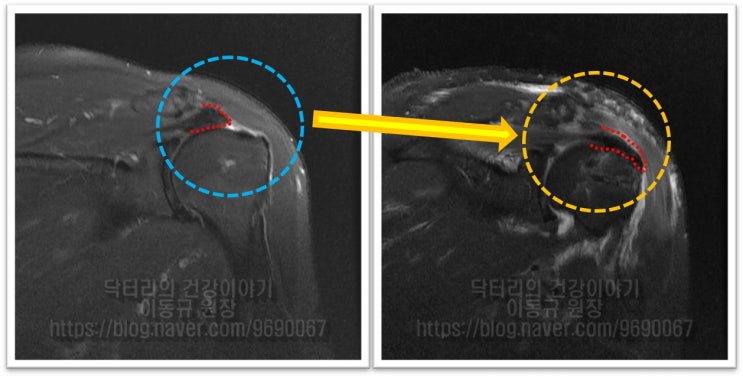

어깨 회전근개 파열 : 보다 단단하게 봉합하는 이열봉합법

안녕하세요. 정형외과 전문의 이동규 입니다. 오늘은 회전근개 파열에서 관절경 수술시 더 단단하게 봉합하...